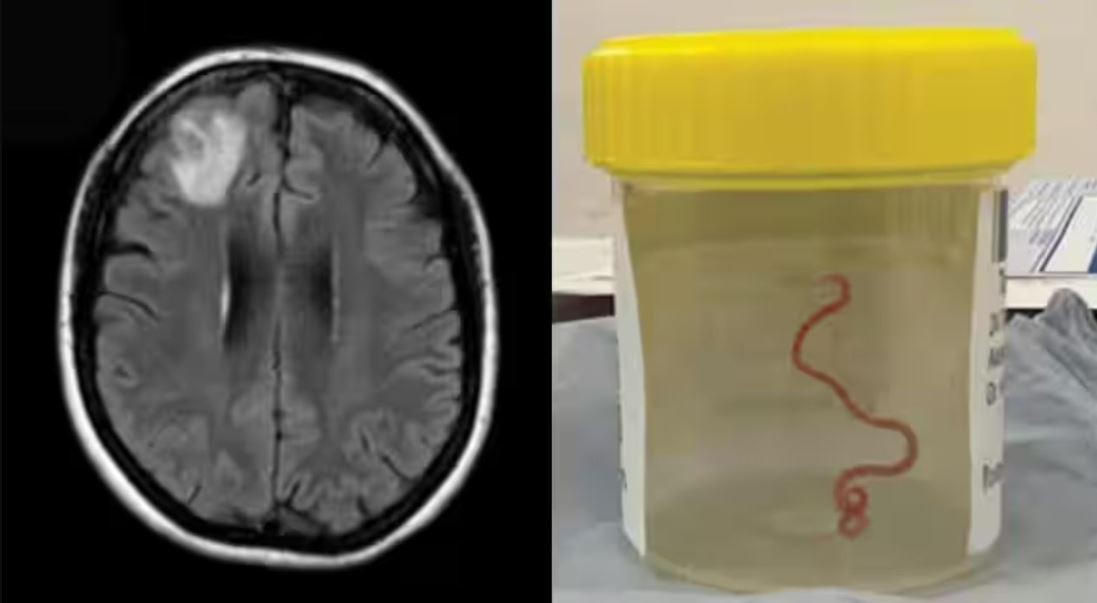

Desconcertados, los médicos realizaron una resonancia magnética a una mujer australiana de 64 años después de que comenzara a sufrir lapsos de memoria y notaron una "lesión atípica" en el frente de su cerebro.

Era una lombriz de ocho centímetros llamada Ophidascaris robertsi, que según investigadores son parásitos comunes en canguros y pitones diamantina pero no en humanos.

Una lombriz parásita usualmente encontrada en serpientes fue retirada "viva y coleando" del cerebro de una mujer, algo que no se había visto en los registros médicos, informaron el martes médicos australianos.